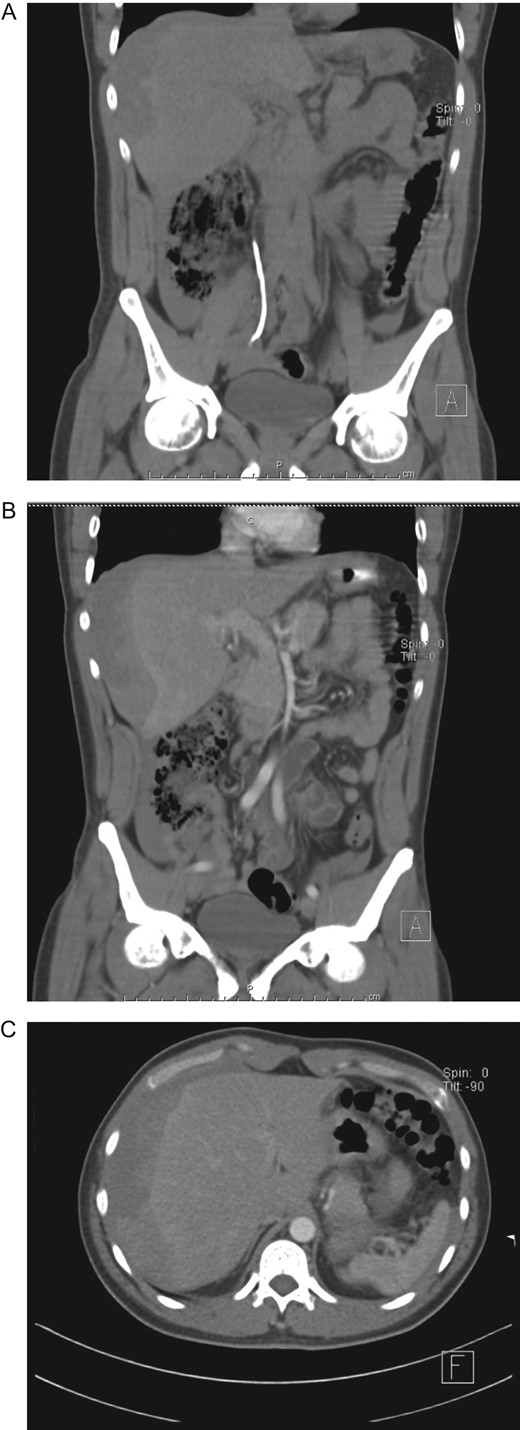

On clinical examination, a dehydrated and tachycardic patient was encountered. He had pain in his right flank that radiated to his lower abdomen and groin. Complete blood count (CBC) and urinalysis appeared normal, however, an abdominal computed tomography (CT) detected bilateral nephrolithiasis, multiple 5 mm, and 6 mm lesions were identified on both the right and left kidney. Also, a 7 mm hyperdense shadow in the middle of the right ureter that caused proximal hydronephrosis was detected as well (Fig. 1A and B).

(A) CT, revealing bilateral nephrolithiasis. (B) CT, with a 7 mm hyperdense shadow in the middle of the right ureter.